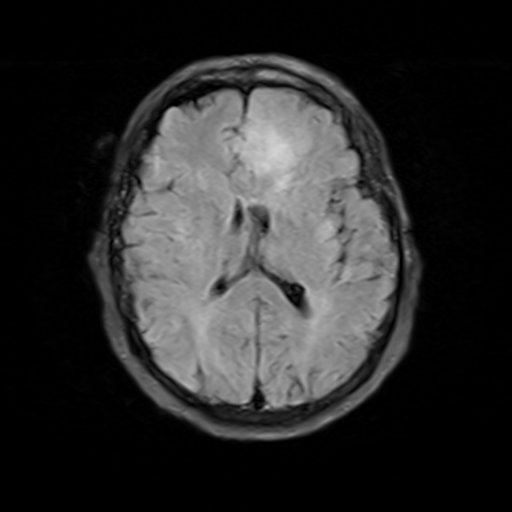

在医学影像领域,条件扩散模型可以用于从低分辨率或噪声图像生成高分辨率的清晰图像,这对于医学诊断具有重要意义。例如,从T1加权MRI图像生成T2加权图像,或者从CT图像生成MRI图像,这些应用可以帮助医生获得更全面的诊断信息。更重要的是,条件扩散模型还可以用于数据增强,生成更多的训练样本,这对于医学影像这种数据稀缺的领域尤其有价值。